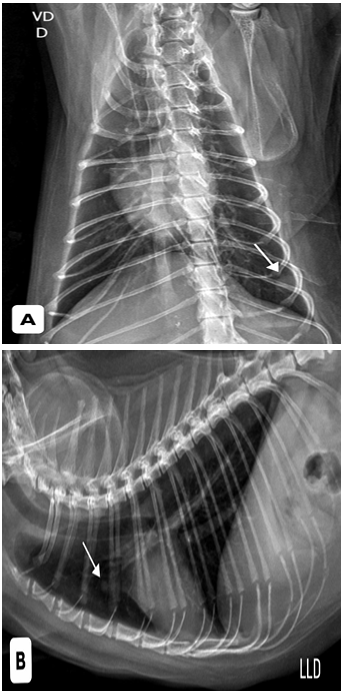

Inicialmente foram realizados dois exames citológicos, os quais apresentaram células inflamatórias e resultados inconclusivos. Foram solicitados exames de triagem oncológica e avaliação pré-anestésica, incluindo hemograma, bioquímicos hepáticos e renais, radiografias torácicas e abdominais, ecocardiograma, eletrocardiograma e ultrassonografia abdominal. Todos os exames apresentavam-se dentro da normalidade para a espécie, entretanto, a radiografia torácica evidenciou duas estruturas arredondadas, radiopacas, sugestivas de metástases pulmonares (Figura 1). A radiografia abdominal mostrou massa de densidade aumentada no abdome caudal esquerdo (Figura 2).

Figura 1: radiografia torácica, visualizadas duas estruturas de maior radiopacidade, arredondadas, sendo a maior medindo aproximadamente 1,0 cm de diâmetro em 9º espaço intercostal esquerdo pela projeção Ventrodorsal (A) e a menor medindo aproximadamente 0,5 cm de diâmetro em região de 3º espaço intercostal pela projeção laterolateral (B).

Fonte: Setor de imagem do Hospital Veterinário Público Anclivepa-SP, 2025.

A avaliação oncológica do paciente com suspeita de SAF deve ser ampla, incluindo hemograma, bioquímica, exames de imagem e sorologias para os vírus da imunodeficiência felina (FIV) e da leucemia felina (FeLV), com o objetivo de estabelecer o estadiamento clínico e investigar a presença de metástases. No caso apresentado, as radiografias torácicas evidenciaram estruturas sugestivas de metástases pulmonares, achado compatível com a literatura, que aponta metástases em até 24% dos casos, principalmente para pulmões, linfonodos regionais, fígado e pelve¹⁸. Tal constatação agravou o prognóstico e reduziu a expectativa de vida do paciente.